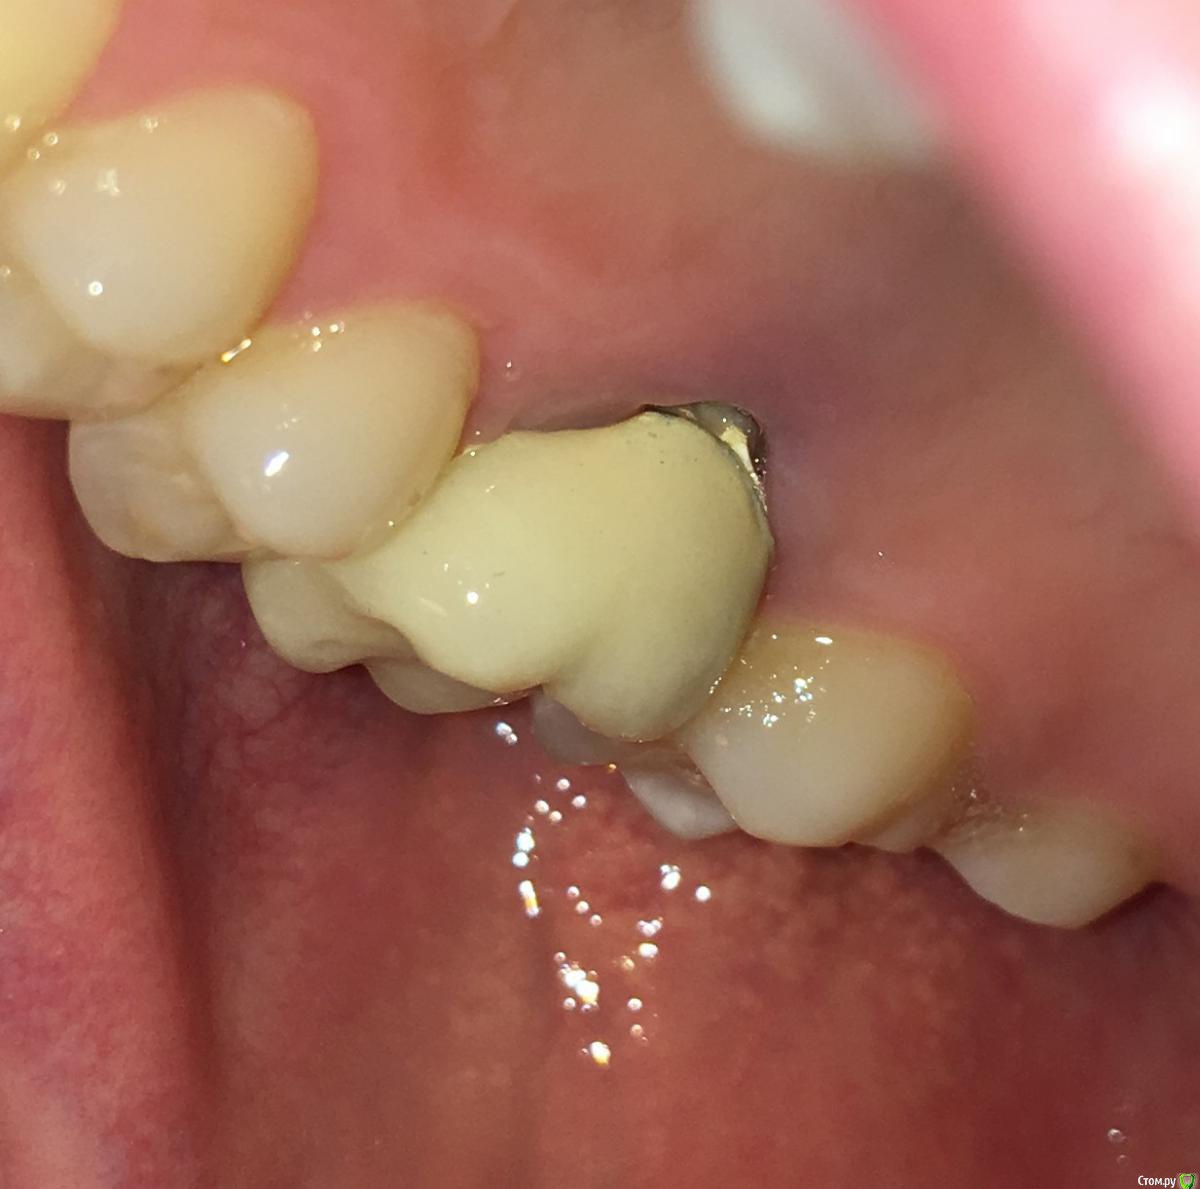

MichaelV Опубликовано 9 октября, 2019 Поделиться Опубликовано 9 октября, 2019 (изменено) Прошу подсказать специалистов.Несколько месяцев назад на 16-ый зуб поставили вкладку (однокоренную) и сделали коронку. Коронка стояла на временном цементе, сейчас отвалилась и надо идти ставить на постоянку. Решил внимательно рассмотреть, как она стоит. С внешней стороны особых вопросов нет - по десне идет тонка темная полоска на стыке коронки и вкладки. С внутренней стороны есть заметная щель. Посмотрите, пожалуйста, фото - нормально ли это или все-таки так быть не должно?Спасибо!(доп. информация - мне 36, нерв был удален лет 15-20 назад, 2 года назад перепломбировал каналы, но вкладку поставил только в этом году. Рад буду услышать рекомендации и советы по продлению жизни зуба в свете текущей ситуации). Изменено 9 октября, 2019 пользователем MichaelV Ссылка на комментарий

chervoncevdaniil Опубликовано 9 октября, 2019 Поделиться Опубликовано 9 октября, 2019 Честно говоря довольно странное решение для одиночной коронки в боковом отделе,это инициатива доктора или ваша была?По теме,может конечно вы ее не до конца одели или временный цемент немного завышает,а на постоянном будет все ОК,но судя по этому фото не совсем точно прилегает коронка Ссылка на комментарий

MichaelV Опубликовано 9 октября, 2019 Автор Поделиться Опубликовано 9 октября, 2019 Скорей всего моя (Семь раз отмерь - один раз отрежь), я всегда настороженно и внимательно отношусь к необратимым вещам, и если можно лишний раз проверить и подстраховаться - лучше так и сделать. Или я в этом случае заблуждаюсь? Тут второй вопрос у меня - насколько реально такую коронку, установленную на постоянный цемент, потом снять и заменить на другую?С внешней сотроны зазор минимальный, как раз м.б. на завышение временного цемента. Такой зазор с внутренней стороны - это очевидный брак, требующей переделки? Ссылка на комментарий